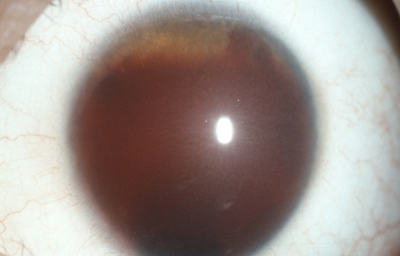

Diastasis del Iris: en un caso de Atrofia Esencial del Iris (Síndrome ICE)

Archivo Fotográfico Dr. Francisco Barraquer